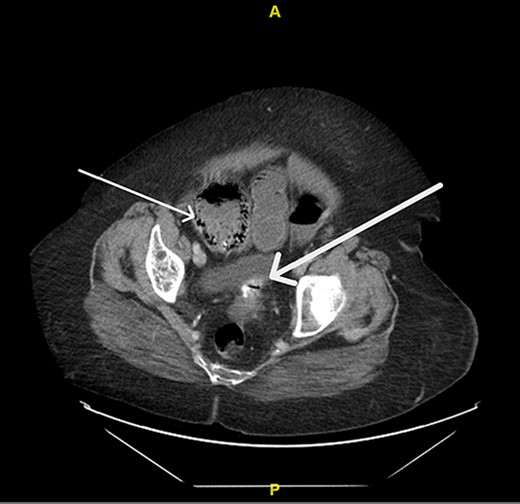

Upon evaluation, the patient was found to have white blood cells 20.1 (4–10.9), with unremarkable vitals and no signs of peritonitis on examination. Computerized tomography (CT) abdomen/pelvis revealed a large bowel obstruction with pneumatosis intestinalis of the right colon secondary to a sigmoid mass (Fig. 1). Upon surgical review of the images, the patient’s CT also showed a left-sided intercostal hernia containing loops of large bowel that was not initially reported by the radiologist (Fig. 2). The mechanism of this was unclear; however, it has been hypothesized that it could be a result of a combination of severe cough related to patient’s recent pneumonia and underlying COPD, or trauma to the left chest wall allegedly sustained at the previous facility.

Left intercostal hernia containing loops of large bowel, axial view (left), coronal view (right).